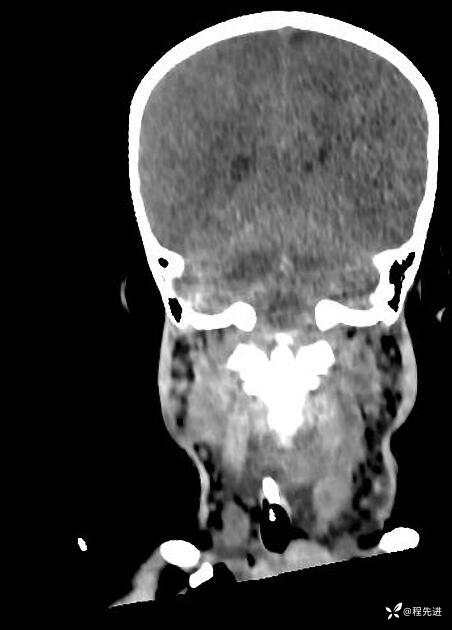

患者性别:男

患者年龄:5岁

简要病史:超速车祸外伤半小时

急诊CT平扫: